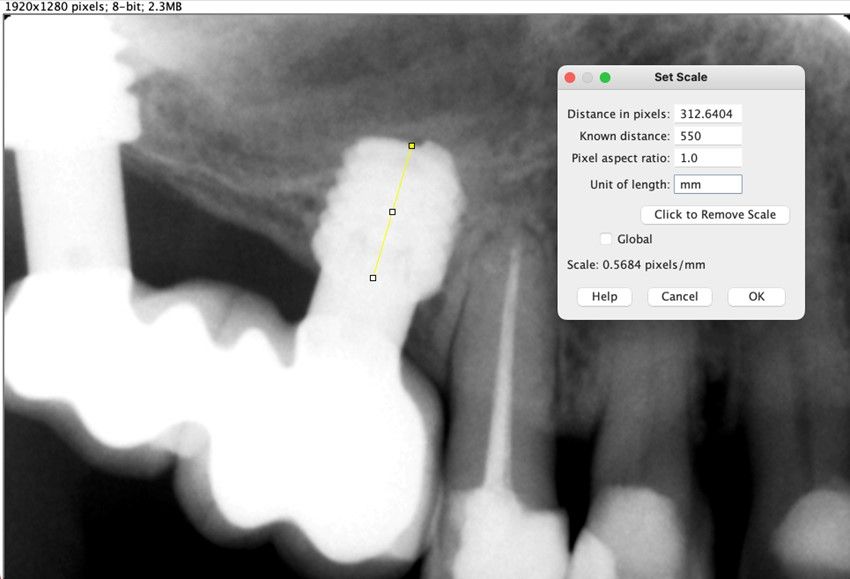

Material y método. Se ha llevado a cabo un estudio retrospectivo de pacientes tratados mediante implantes extracortos (5,5 y 6,5 mm de longitud) colocados mediante elevación transcrestal sin el uso de injerto. Como variables principales se han estudiado: la pérdida ósea crestal de los implantes y la ganancia en altura sobre el ápice. Como variable secundaria se ha estudiado la supervivencia de los implantes.

Resultados. Fueron reclutados 13 pacientes en los que se insertaron 30 implantes. Una vez insertados y cargados los implantes, la altura media final fue de 9,68 mm (+/- 2,66), lo que supone una ganancia promedio de 5 mm. A los 10 años, se observó una disminución media de la altura ósea ganada en los implantes en conjunto de 0, 29 mm (+/- 0,77). La media de la pérdida ósea mesial fue de 0,73 mm (+/- 0,75 mm) y la media de la pérdida ósea distal fue de 0,98 mm (+/- 1,2 mm). La supervivencia fue del 100%.

Material and methods. A retrospective study of patients treated with extra-short implants (5.5 and 6.5 mm in length) placed by transcrestal elevation without the use of a graft was carried out. The main variables studied were: the crestal bone loss of the implants and the gain in height above the apex. Implant survival was studied as a secondary variable.

Results.Thirteen patients were recruited and 30 implants were inserted. Once the implants were inserted and loaded, the mean final height was 9.68 mm (+/- 2.66), which represents an average gain of 5 mm. At 10 years, there was a mean decrease in the overall bone height gain of the implants of 0.29 mm (+/- 0.77). The mean mesial bone loss was 0.73 mm (+/- 0.75 mm) and the mean distal bone loss was 0.98 mm (+/- 1.2 mm). Survival was 100%.

Nuestro grupo de estudio modifica esta técnica de elevación transcrestal utilizando para el acceso unas fresas de corte frontal que permiten eliminar la cortical inferior del seno con lentitud sin dañar la membrana de Schneider, eliminándose los osteotomos y el malestar que genera su accionamiento mediante el martillo6-7. Inicialmente el procedimiento fue concebido para ser empleado con material de injerto al igual que el abordaje convencional, pero posteriormente se presentaron variaciones del procedimiento donde se insertaban los implantes sin injerto, utilizándose el propio implante como mantenedor de espacio entre la membrana de Schneider y la cavidad creada entre la membrana y la cresta, permitiendo que esta cavidad no se colapsase y posteriormente fuera colonizada por nuevo hueso7-11.

Los senos tratados con la técnica de elevación transcrestal sin material de relleno muestran un incremento de entre 2,5 mm12,13 hasta 4.4 mm14,15 en la altura ósea lograda sobre el ápice y una supervivencia de los implantes que se sitúa entre un 94 y un 100%16-17. En este trabajo se presenta un estudio retrospectivo donde se ha evaluado la inserción de implantes extracortos (5,5 y 6,5 mm) en zonas posteriores maxilares mediante la técnica de elevación de seno transcrestal con la fresa de ataque frontal sin la utilización de material de injerto, con un tiempo de seguimiento de 10 años para poder objetivar el comportamiento de los implantes a largo plazo y de la técnica empleada.